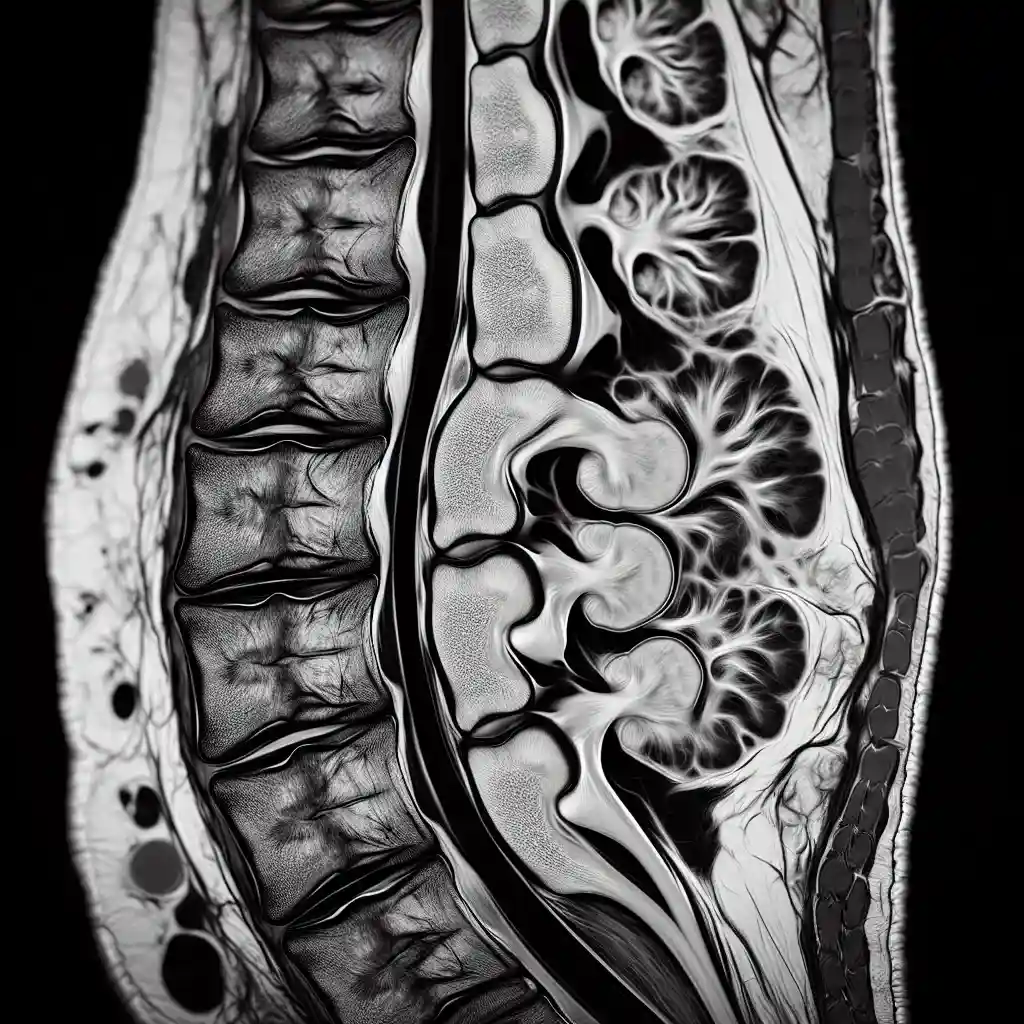

Грижа хребта на МРТ

Грижа хребта – це поширена проблема, яка часто діагностується за допомогою МРТ. Цей метод візуалізації дає можливість лікарю отримати детальну картину стану хребта і міжхребцевих дисків. Грамотна діагностика допомагає вибрати ефективне лікування та уникнути ускладнень. Якщо ви підозрюєте у себе грижу хребта, важливо розуміти, як роблять МРТ і що показують знімки. Пропонуємо детальний огляд особливостей грижі хребта на МРТ, що допоможе вам краще орієнтуватися в цій процедурі.

Застосування МРТ в діагностиці міжхребцевої грижі дозволяє побачити навіть найменші зміни, а лікарі в Україні активно використовують цей метод для точного визначення стану пацієнтів. Якщо ви хочете дізнатися більше про те, як виглядає грижа хребта на МРТ, читайте далі!